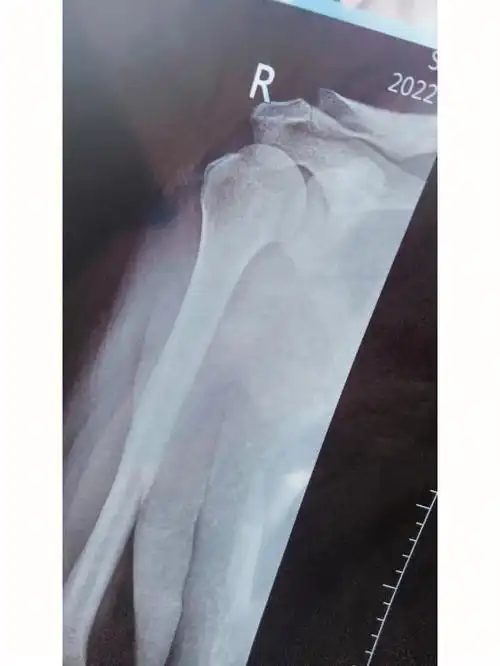

平举正常,伴有疼痛,外展120度左右,肩膀僵硬感觉,骨折周围轻微骨质